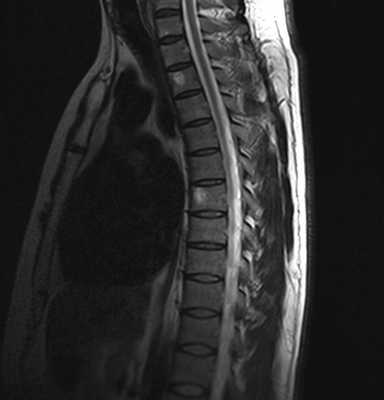

Ведущими в МРТ позвоночника всегда являются сагиттальная (вдоль тела) а аксиальная (поперечная) плоскости, дополнительной может быть корональная (фронтальная) плоскость. Физические основы МРТ и получение МРТ изображения изложены в наших статьях, однако, они предназначены для подготовленного читателя. Разглядывая МРТ изображение позвоночника, Вы увидите, что спинномозговая жидкость (ликвор) на одних из них светлый (почти белый), на других, наоборот, темный. Так можно различить Т2-взвешенные и Т1-взвешенные МРТ изображения. Очень важно понимать, что это не негатив и позитив, а МРТ изображения, зависимые от разных физических характеристик, и потому несущие в себе разную информацию. На снимке (вернее сказать, отпечатке) или на CD диске, сняты или записаны серии однотипных по способу получения МРТ изображений позвоночника. Срезы идут друг за другом, например, справа налево в сагиттальной плоскости. Обычно для облегчения понимания где проходит данный срез в углу картинки дается референтное изображение, оно показывает линию этого МРТ среза в другой, перпендикулярной ему плоскости. Иногда делается дополнительное референтное МРТ изображение на котором показаны все срезы с их нумерацией. Зазор между срезами меньше 1 мм или вовсе отсутствует. Толщина среза выбирается оптимальной в зависимости от исследуемого отдела позвоночника, плоскости и МРТ аппарата. Обычно при МРТ позвоночника она 3-4 мм. В любом случае, выбираемый оператором или врачом протокол МРТ (то есть набор плоскостей и последовательностей), соответствует задачам данного МРТ исследования. Оценка качества МРТ изображения не может быть осуществлена ни пациентом, ни врачом-клиницистом. Заключение, данное врачом-рентгенологом, подразумевает, что само изображение было приемлимым для выводов. Хотелось бы особо подчеркнуть, что Заключение в конце Описания, выдаваемое пациенту, не является диагнозом, а лишь выводами врача- рентгенолога на основе интерпретации им изображений. Диагноз ставится врачом-клиницистом на основании всех имеющихся медицинских данных - жалоб, клинического осмотра, заключений других специалистов, лабораторных анализов, заключений по МРТ и другим изображениям. При этом расхождения между заключениями по результатам разных исследований явление вполне нормальное.

Грудной отдел позвоночника на МРТ в коронарной проекции